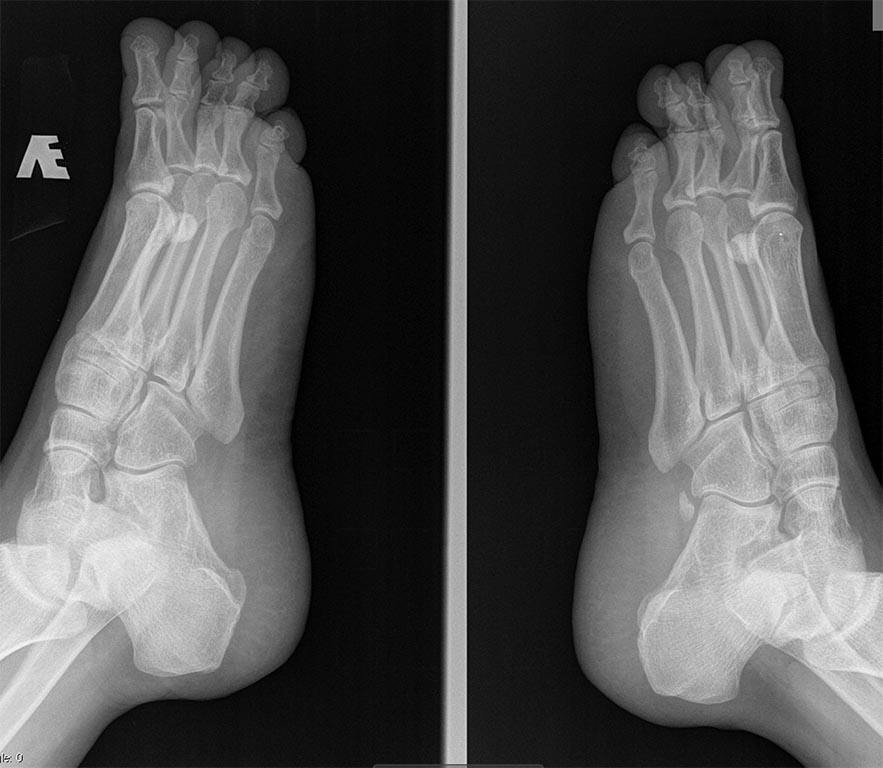

Пациентка 40 лет, жалобы на длинные 4 пальцы обеих стоп, трудности с

подбором обуви, чисто косметический дефект, болей натоптышей нет. За

счет чего лучше сделать укорочение, плюсневой кости и основной фаланги

(если фаланга чем фиксировать).